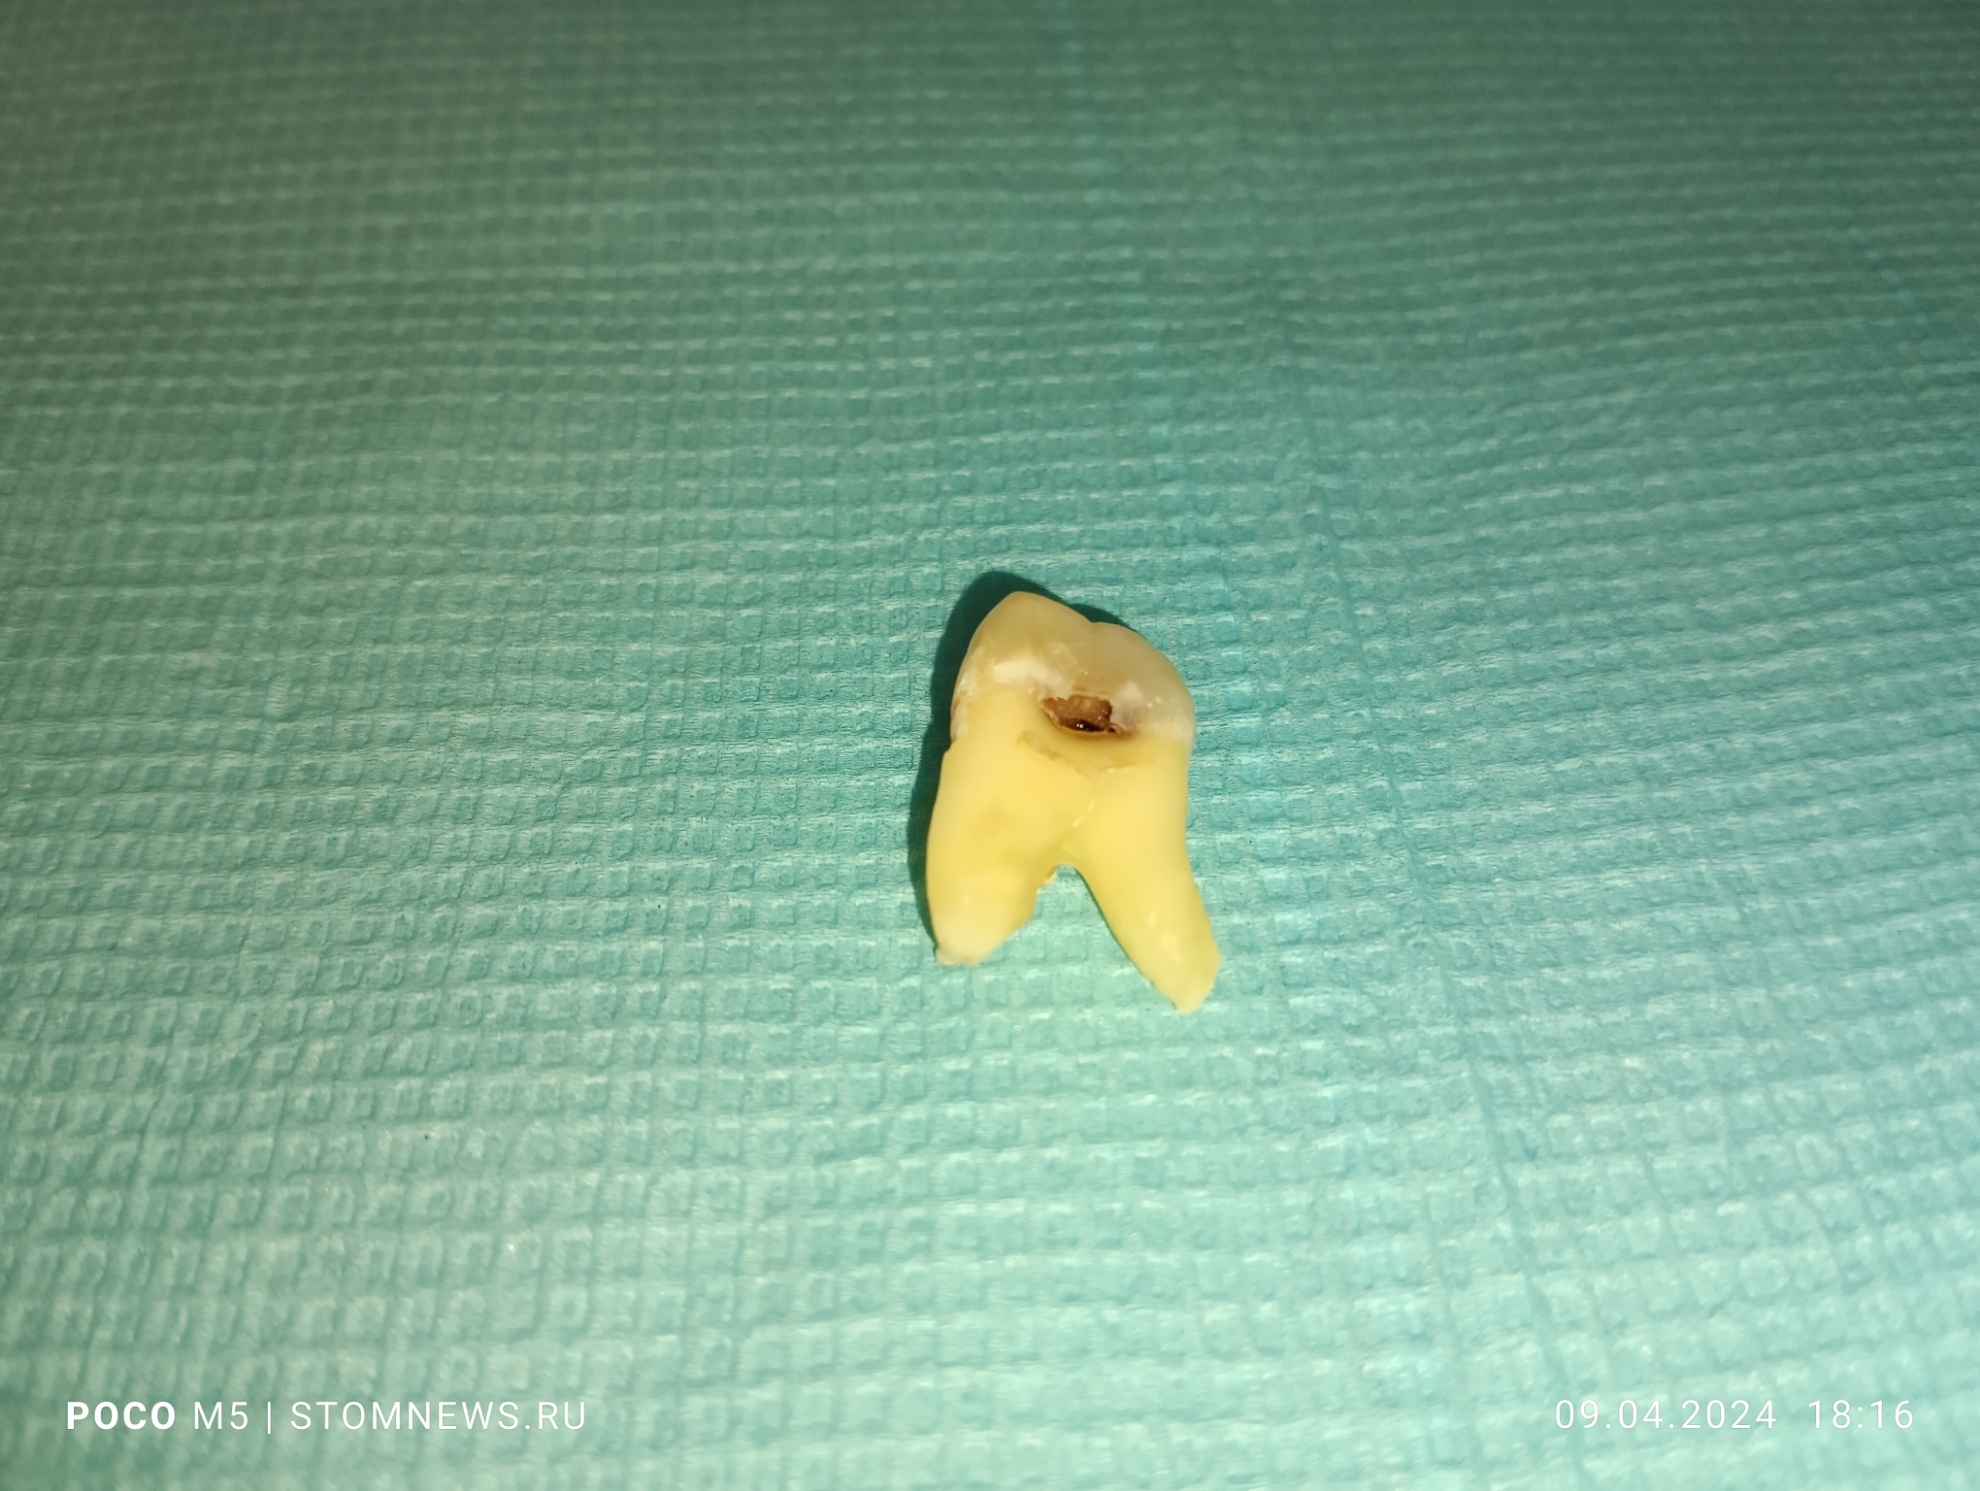

Удаленный 28 зуб мудрости с корнями по типу «оленьи рога»

💥Вот такой клинический случай произошел у меня на приеме сегодня: 09.04.20024 💥

😬Как оказалось, у пациента слева вверху запряталась восьмерка, которая только не давно прорезалась. При пальпации слизистой в области 28 зуба пациент резко дёргался 😱😱😱

☄️Было принято решение об удалении, так как спасти его не представлялось возможным👊

✌️Я решил сделать серию фотографий и выложил их на свой собственный сайт в виде галереи. Если вам интересно посмотреть поближе на этого монстра, то переходите по ссылке ниже👇👇👇